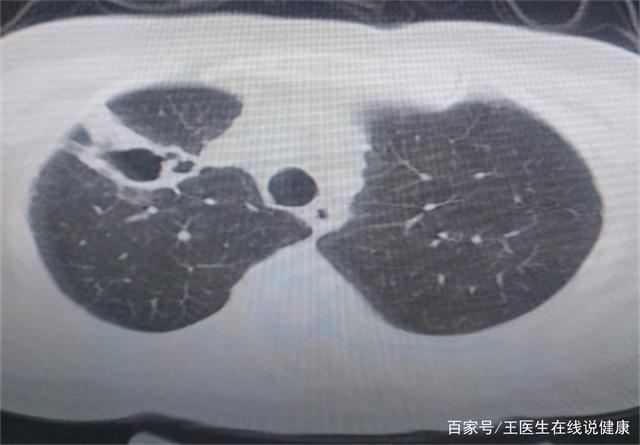

空洞是影像学上可以看到肺部有 空心部位,当肺部病变组织坏死后气体流